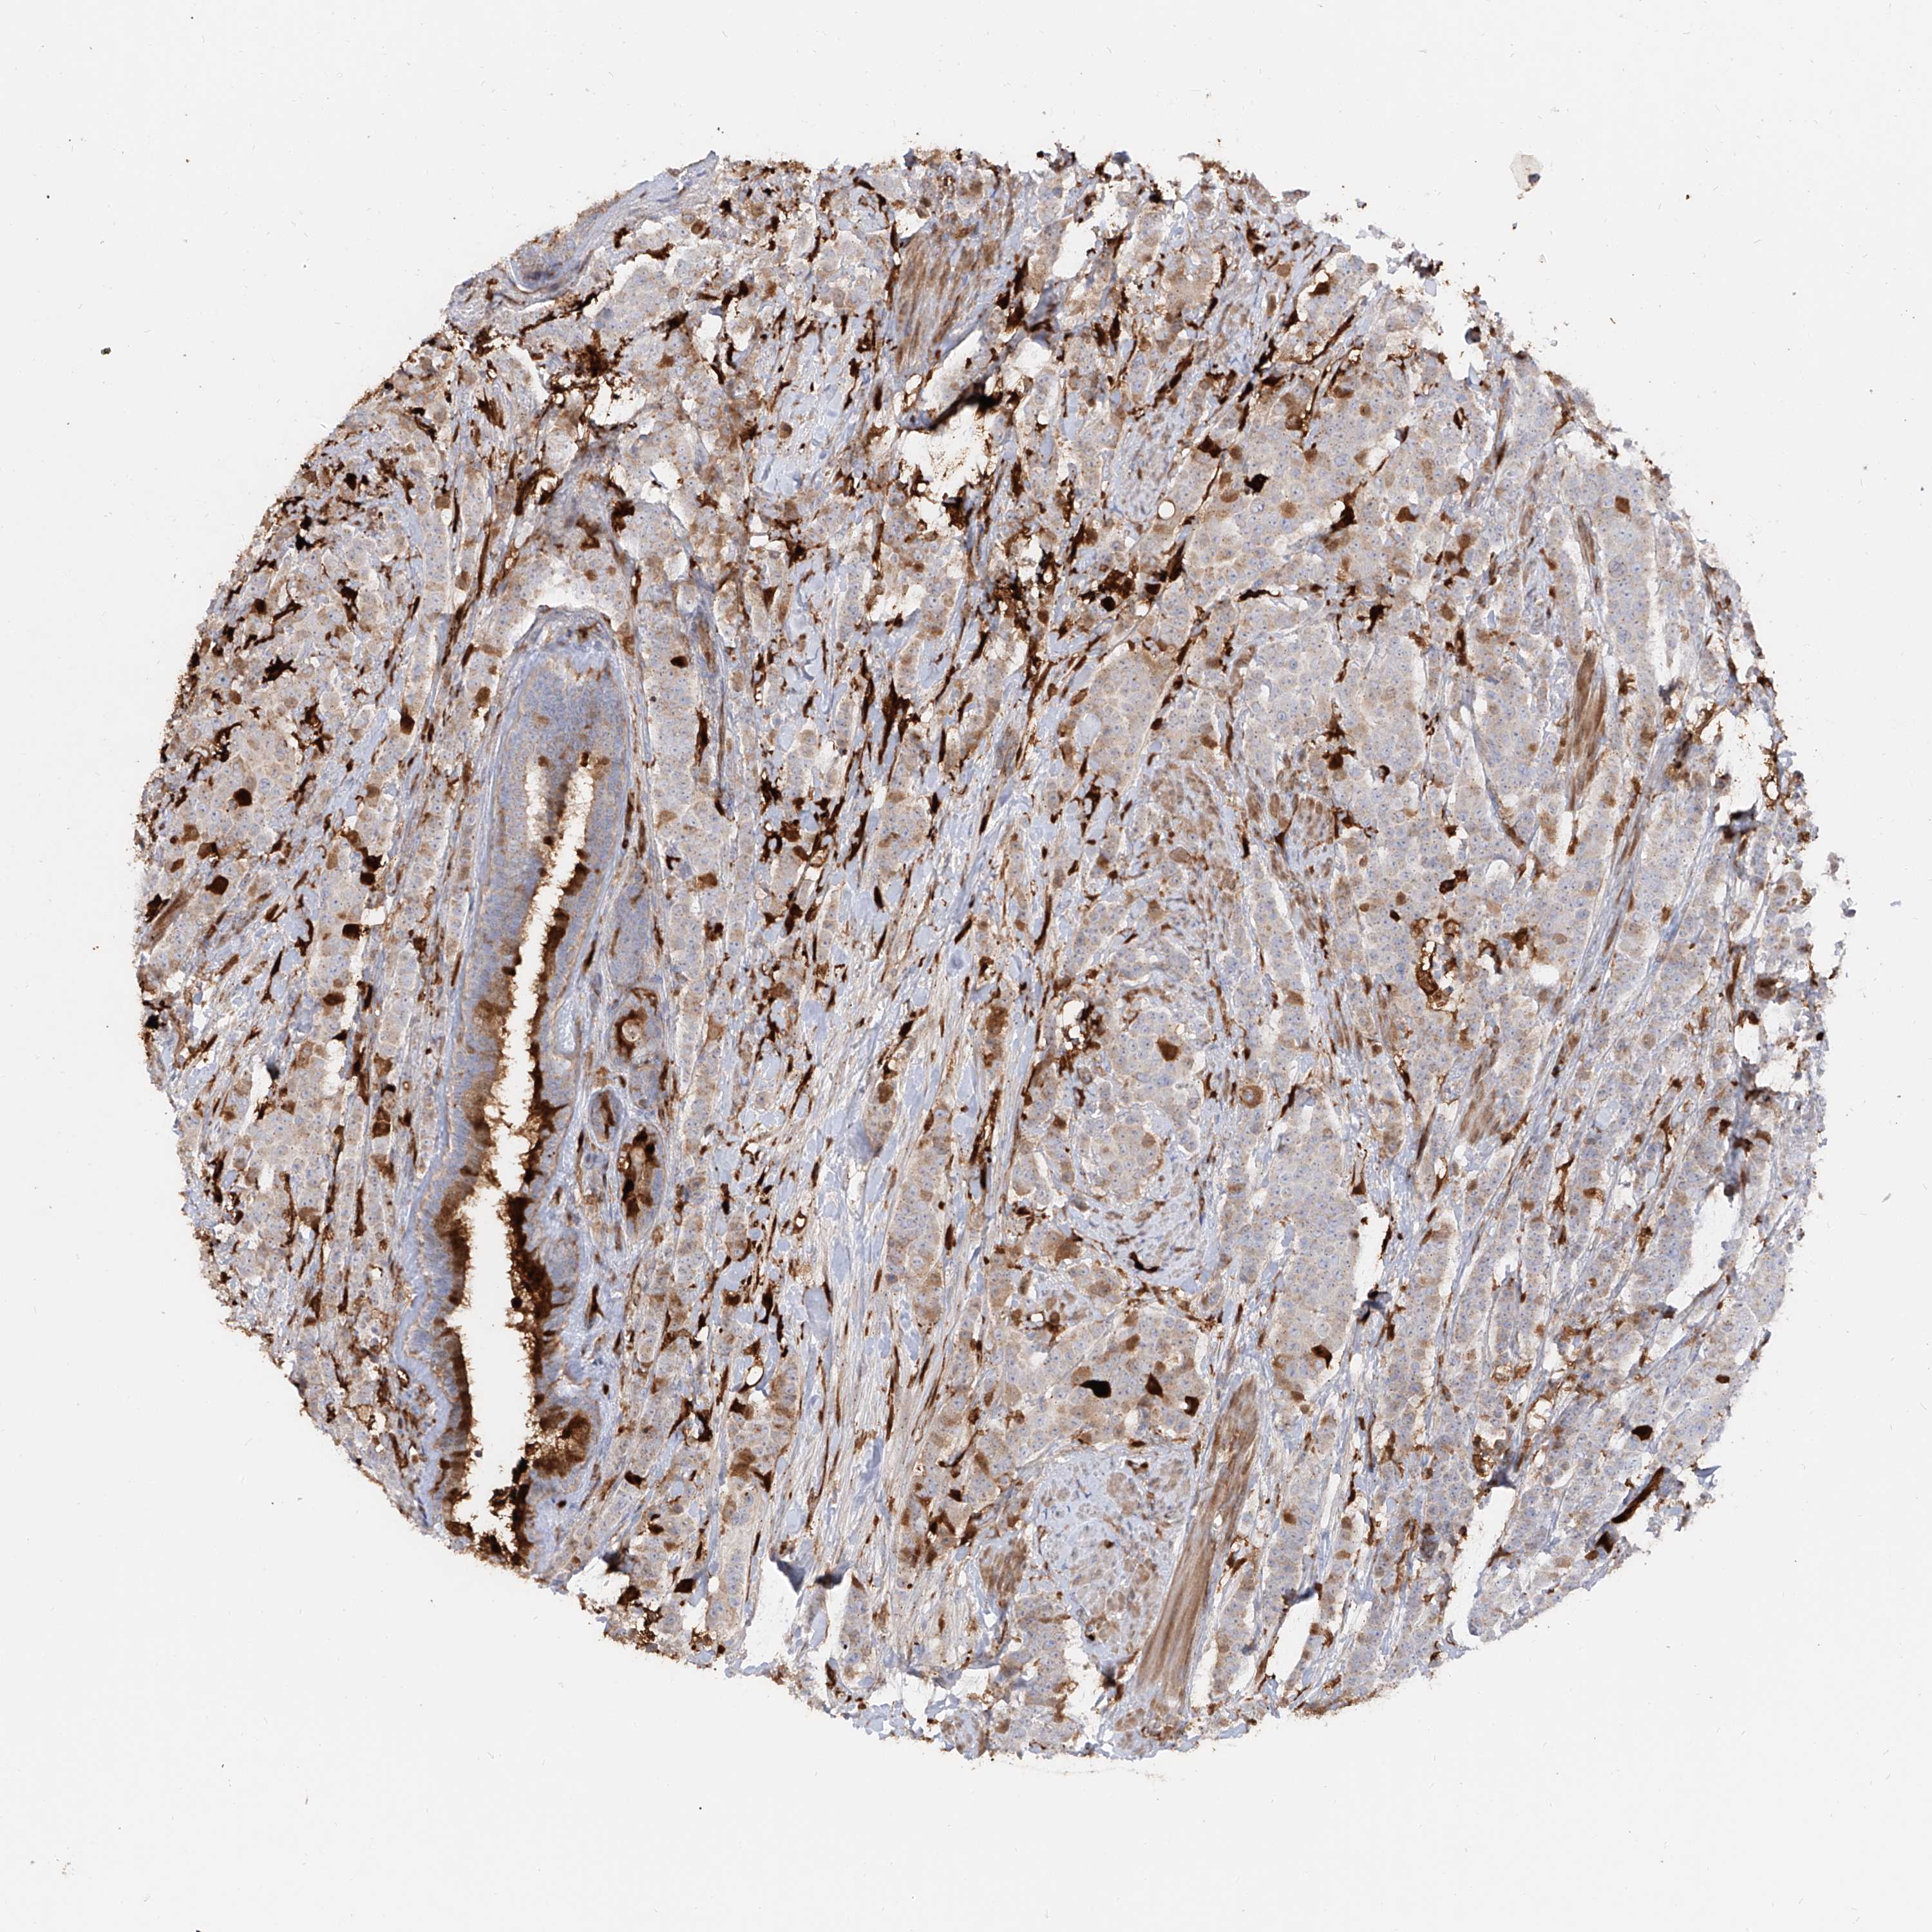

BRCA TCGA BRCA VALIDATION PROTEIN EXPRESSION